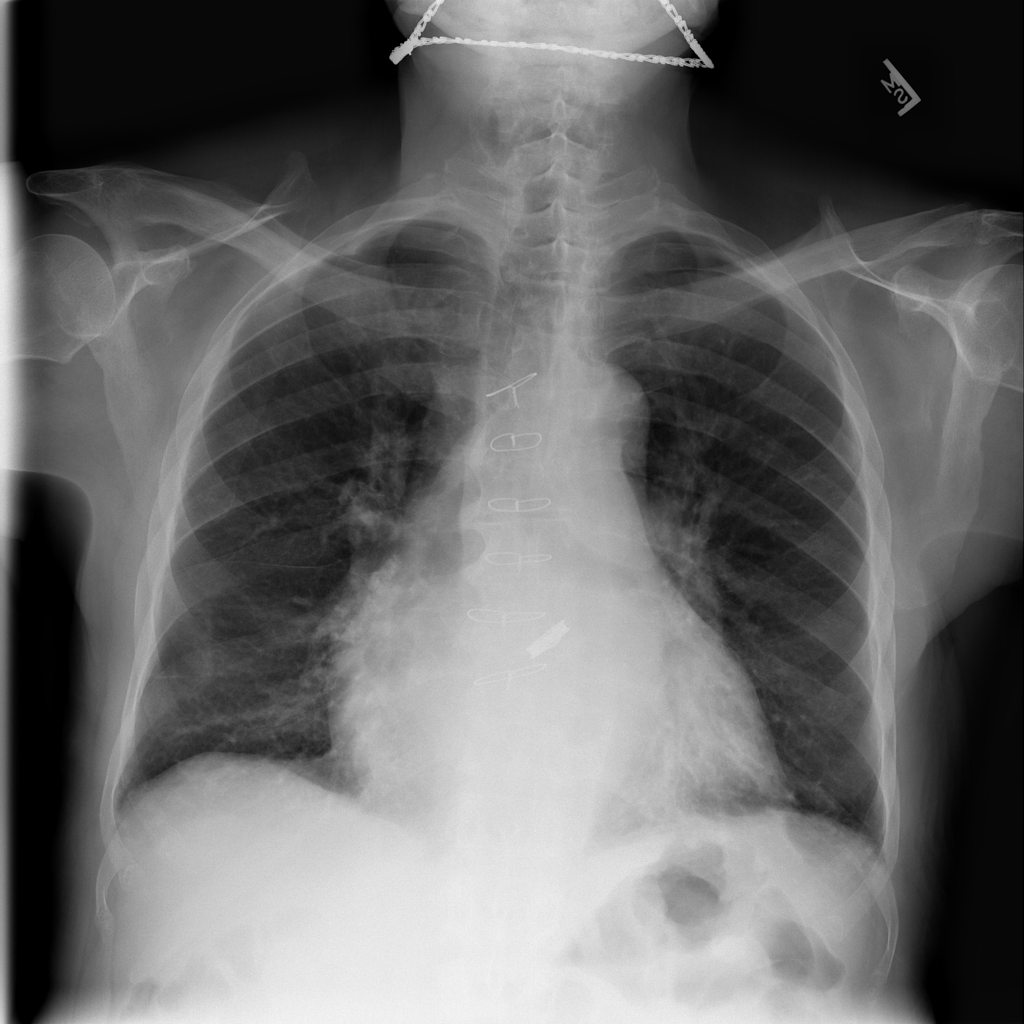

PAT-4639 · IMG-045Cardiomegaly

PAT-4639 · IMG-045

PA